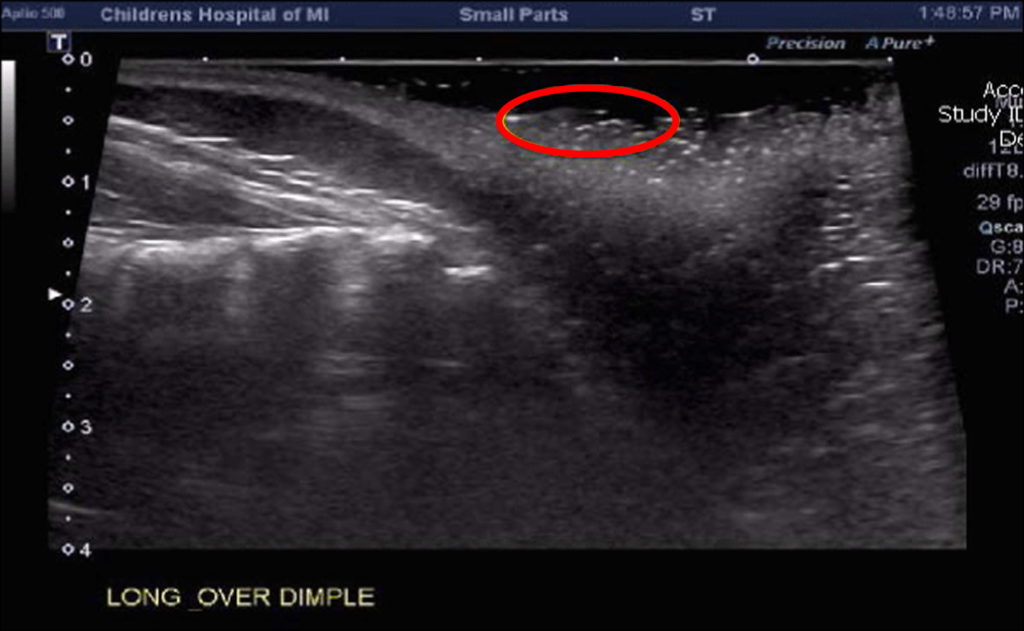

Sacral Dimple Ultrasound Why Do Sacral Dimples Occur Sacral refers to the sacrum, which is. A single sacral dimple can occur with some medical conditions affecting the spinal. A sacral dimple, also known as a pilonidal dimple, is a small indentation or pit in the skin on the lower back, typically located just above the. A sacral dimple is a small, usually shallow indentation in the small of. Why Do Sacral Dimples Occur.

Sacral Dimple Ultrasound Why Do Sacral Dimples Occur A sacral dimple is a small bump in your newborn’s lower back near the crease of their buttocks. Sacral refers to the sacrum, which is. Sacral and back dimples are congenital, which means you are born with them. A single sacral dimple can occur with some medical conditions affecting the spinal. Sacral dimples are small clefts at the base of. Why Do Sacral Dimples Occur.

The Sacral Dimple A Sonographer’s Perspective Why Do Sacral Dimples Occur A sacral dimple, also known as a pilonidal dimple, is a small indentation or pit in the skin on the lower back, typically located just above the. What causes sacral or back dimples? They are a congenital condition, meaning most people are born with. A sacral dimple is a small, usually shallow indentation in the small of the back,. Sacral. Why Do Sacral Dimples Occur.

Figure 2 from Sacral Dimplethe Role and Yield of Imaging Semantic Why Do Sacral Dimples Occur A sacral dimple, also known as a pilonidal dimple, is a small indentation or pit in the skin on the lower back, typically located just above the. A sacral dimple is a small bump in your newborn’s lower back near the crease of their buttocks. A single sacral dimple can occur with some medical conditions affecting the spinal. Sacral refers. Why Do Sacral Dimples Occur.